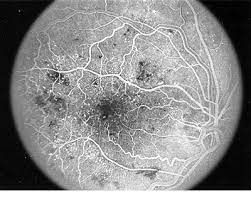

آنژیوگرافی فلورسین

آنژیوگرافی فلورسین (Fluorescein angiography)

(یا: رگنگاری فلورسین؛ رگنگاری با ماده فلورسنت) روشی تشخیصی برای بررسی عروق خونی چشم. پزشک پرتغالی متخصص مغز و اعصاب، ایگاز مانیس[۱] در 1927م اولین بار در شهر لیسبون از این شیوه استفاده کرد. کارآیی آن باعث توجه بیشتر و تکامل آن شد؛ به طوری که آخیم وسینگ[۲]، چشمپزشک آلمانی، در سال 1969م تکمیلشدۀ آن را ارائه کرد. با این فناوری توانستهاند رگهای سطح داخلی چشم[۳]، شامل شبکیه، مشیمیه و لکۀ زرد (ماکولا[۴]) را عکسبرداری و معاینه کنند. نشت رگهای مشیمیه، لکۀ زرد و شبکیه، که معمولاً بر اثر پیری یا دیابت باعث اختلال در دستگاه بینایی میگردند، از این طریق معاینه میشوند.

روش اجرا اینگونه است که: فلورسنت به رگ بازویی تزریق و با حرکت در بدن، در رگهای داخل چشم هم جریان مییابد. رگها به رنگ سبز-آبی درخشان شده و با دوربینی، عکسبرداری و وضعیتشان تشخیص داده میشود.